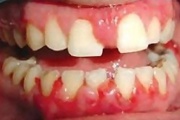

Krooniline gingiviit

Äge krooniline gingiviit

igemete veritsus kroonilise gingiviidiga patsiendil

Gingiviit ehk igemepõletik